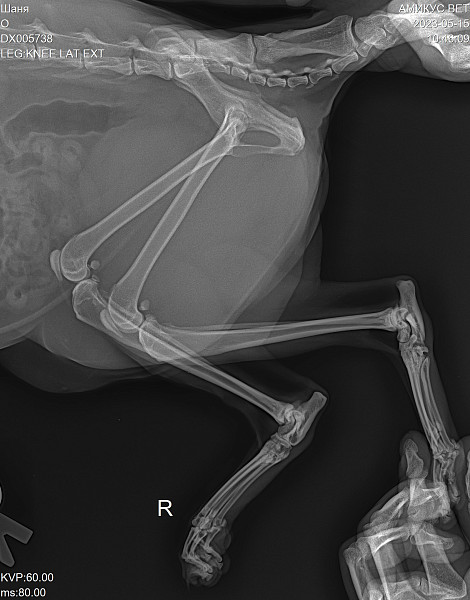

Истончение костей у кошек: причины и решения

Раздел: Мудрость в объективе